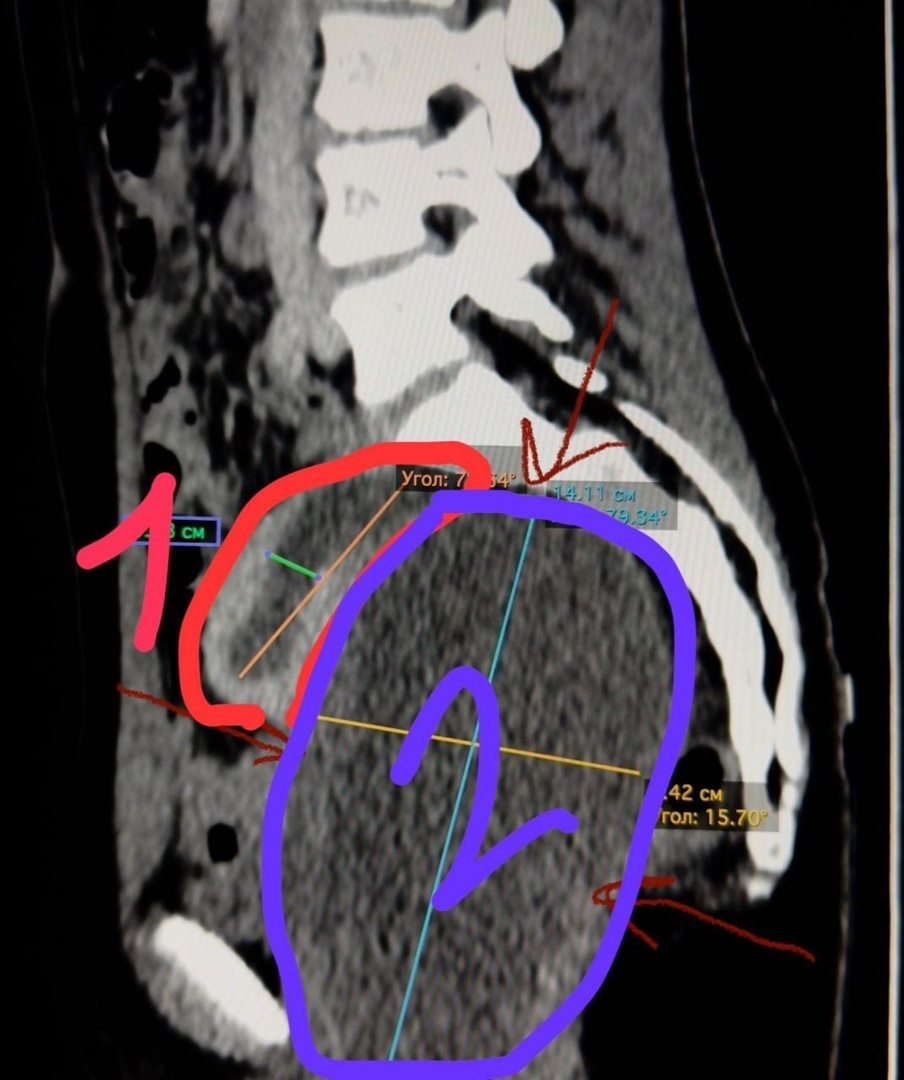

Хотя анализы были в норме, обезболивающие не помогали. Сделали УЗИ брюшной полости и малого таза. Оно показало образование 15 на 8 см. Матка была увеличена.

Диагноз – гематокольпос, гематометра. При нем менструальная кровь скапливается в матке и влагалище, вместо того, чтобы покинуть организм.

Хотя анализы были в норме, обезболивающие не помогали. Сделали УЗИ брюшной полости и малого таза.

Оно показало образование 15 на 8 см. Матка была увеличена.